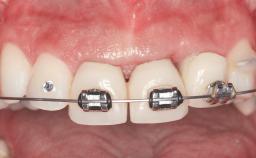

Replacement of Four Incisors with a Fixed Partial Denture on Two Narrow-Neck Implants after Implant Failure

| Area | Anterior |

| # of Teeth | 4 |

| # of Implants | 2 |